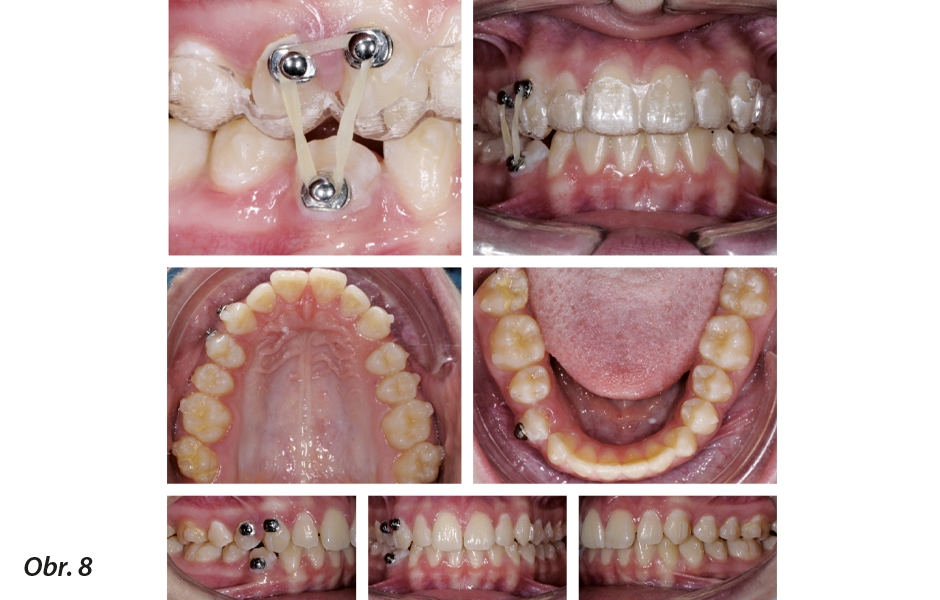

Knofl íky a gumičky na místě s ortodontickými fóliovými aparáty Invisalign® během léčby

Po intruzi horních premolárů byla chirurgicky odstraněna dolní folikulární cysta a jakmile byl zub izolován, byl ke koronálnímu aspektu připojen zlatý řetízek. Řetízek vystoupil přes řez ve střední oblasti hrany a na spodní ortodontický fóliový aparát byla připevněna elastická trakce. Když byl zub částečně vytažen a řetízek již nebyl potřeba, byl odstraněn a na bukální aspekt dolního prvního premoláru a horního premoláru byl připevněn knoflík. Ortodontické fóliové aparáty byly upraveny tak, aby do nich bylo možno umístit knoflíky, a k dokončení pohybu vytlačení byla použita gumička o velikosti 3/16 inch a hmotnosti 3 oz. (obr. 8). -

Pacientka byla poučena, aby ortodontický fóliový aparát nosila alespoň 21 hodin denně. U této pacientky byly první dvě fáze předepsány na delší dobu nošení s pečlivým pozorováním za účelem vyhodnocení sledování zubů a dodržování pravidel na straně pacientky. Od třetího ortodontického fóliového aparátu se ortodontické fóliové aparáty začaly vyměňovat po týdnu. - Příchytky: K horním stoličkám a dolním druhým stoličkám byly připojeny obdélníkové a vodorovné příchytky. K horním špičákům a dolním prvním stoličkám byly připojeny obdélníkové a vodorovné příchytky. Optimalizované příchytky byly umístěny na premoláry a dolní špičáky. Ve 2. fázi byly konvenční a optimalizované příchytky umístěny na stejných zubech jako v 1. fázi a byly použity pro účely dokončení.

Výsledek léčby

Případ byl dokončen ve vztahu špičáků a stoliček třídy I s funkčním předkusem. Vklíněný dolní pravý první premolár byl přetažen do oblouku bez rovnátek nebo drátků. Řetízek byl k ortodontickému fóliovému aparátu upevněn pomocí 1/4 inch, 4,5 oz gumiček. Ortodontické fóliové aparáty byly upraveny čirými kleštěmi na aparáty, aby se vytvořily háčky pro ukotvení gumiček. Pacientka byla poučena, aby vyměňovala gumičky nejméně třikrát denně, aby se udržela konstantní síla na vklíněný premolár. Jakmile byla okluzní třetina bukálního povrchu vytažena, byl na bukální aspekty dolního vklíněného premoláru a horních premolárů umístěn knoflík, aby bylo možno použít gumičky k dokončení řízeného vytažení spodního premoláru (3/16 inch, 3 oz). Ortodontické fóliové aparáty byly pomocí čirých kleští na aparáty upraveny, aby bylo možno umístit knoflíky. Bylo dosaženo dobré konečné interkuspidace, aby byla zaručena ortopedická stabilita. Kromě toho byl úsměv značně vylepšen dokonalou kontrolou bukolingválního sklonu horních a dolních řezáků, jak ukazuje cefalometrická analýza (obr. 9–11).

Použití příchytek na všech premolárech a stoličkách je užitečné k řízení maxilární expanze během bukálního pohybu, který vyvíjí vytlačovací sílu na tyto příchytky. Výsledkem je vytvoření několika sil generujících pohyb, čímž se usnadní bukolingvální řízení premolárů a stoliček. Jinými slovy lze dosáhnout řízeného bukálního pohybu jejich kořenů. Extruzní síla navíc zlepší finální interkuspidaci v oblasti premolárů a molárů, čímž se sníží účinek skusového bloku popsaný u ortodontických fóliových aparátů. Tento případ ukazuje, jak je možno provést ortochirurgickou trakci vklíněného dolního premoláru pomocí ortodontických fóliových aparátů, knoflíků a gumiček bez rovnátek a drátků. Pacientka i její rodiče to velice ocenili. Pohodlná a estetická řešení mohou být pro dospívající základním požadavkem.